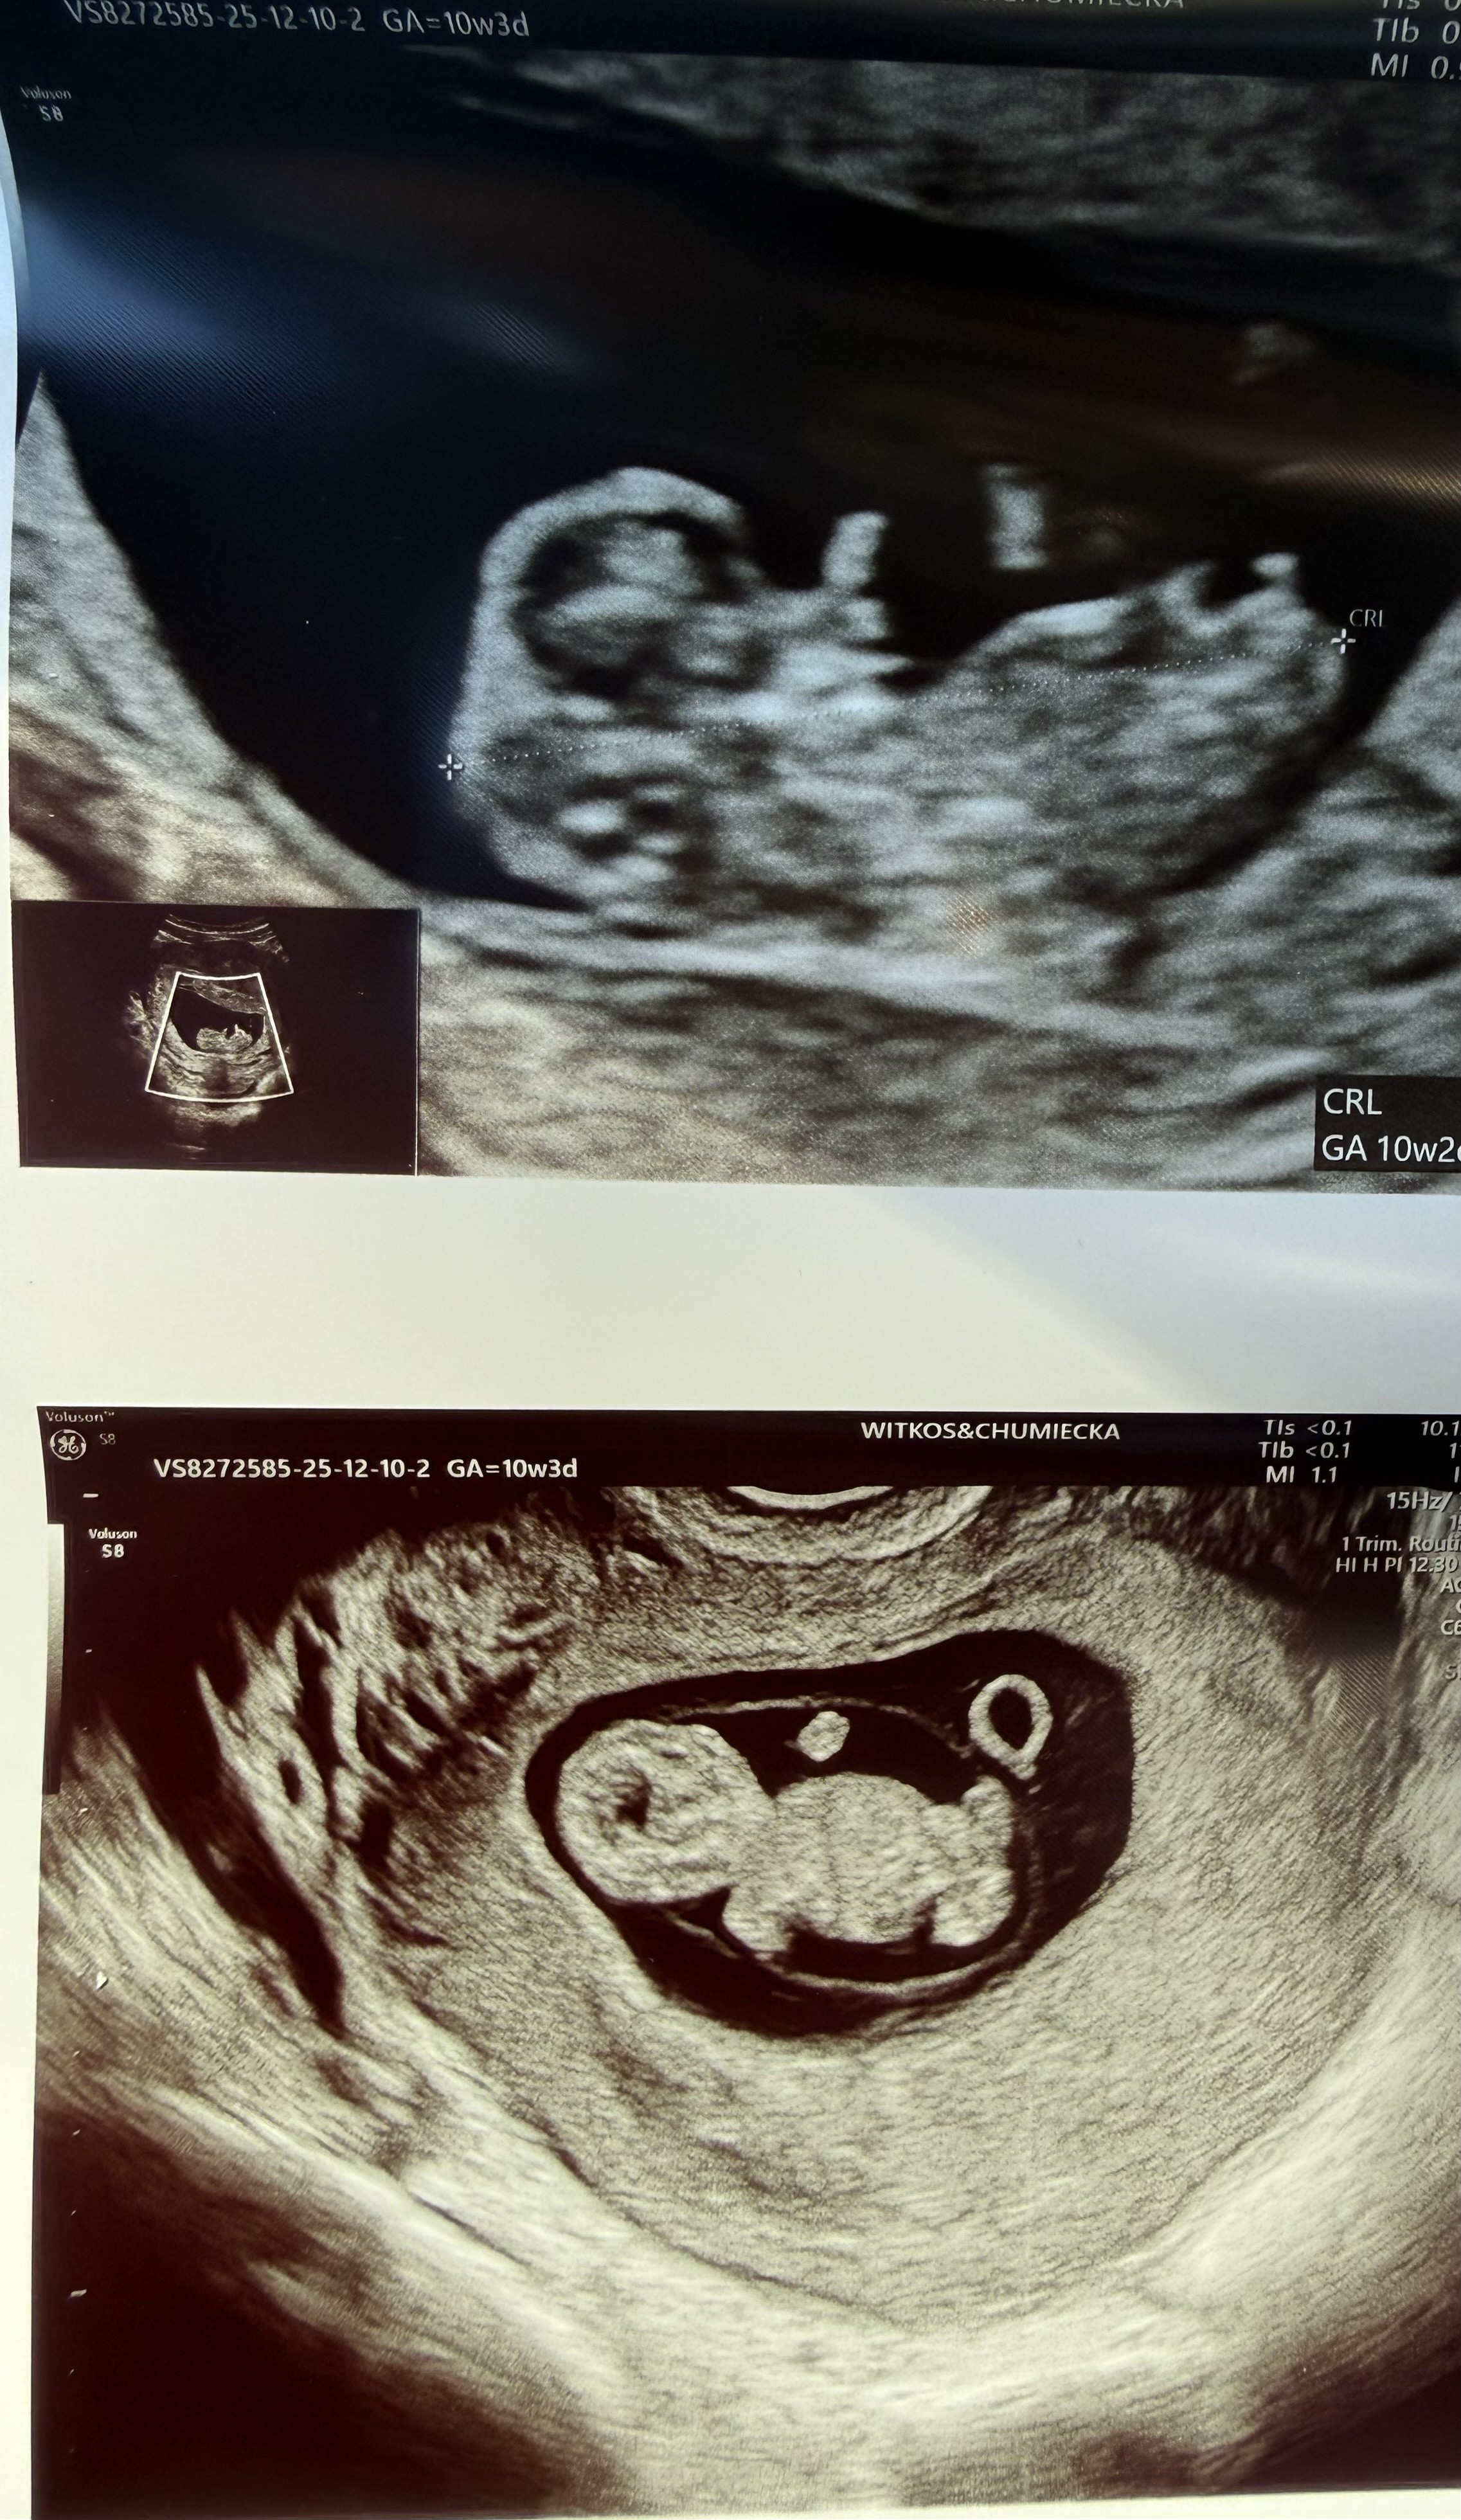

Hejka:) wczorajsza wizyta mnie bardzo uspokoiła wszystko jest ok:) potem byłam

na prenatalnych i teraz czekam z niecierpliwością na wyniki i usg prenatalne☺️ A dzisiaj dostałam takiego powera, że nagotowałam, psie fryzury ogarnęłam i polatałam po lesie 10 km jak przed ciążą bez zadyszki🥰